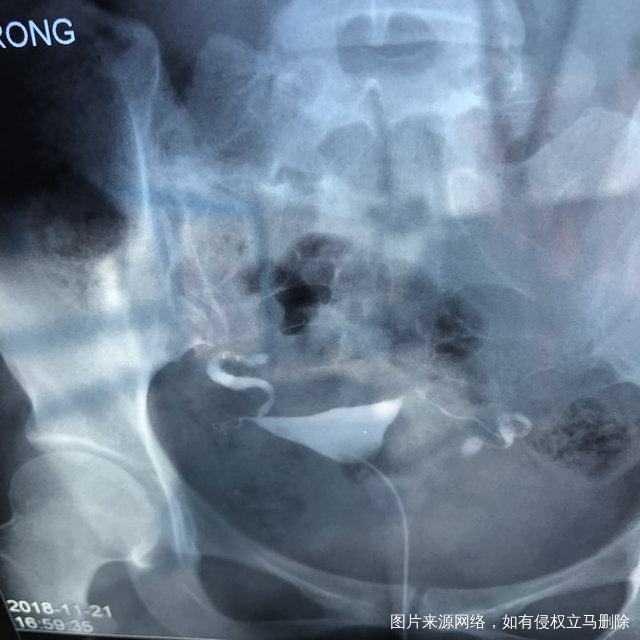

麻烦各位教授给我看看输卵管造影片子,谢谢了🙏